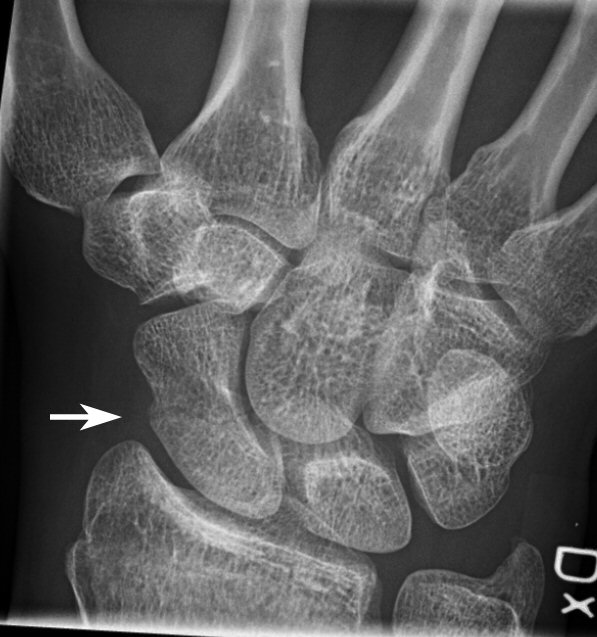

Midjefrakturer i skafoideum. Båda behandlade med gips, andra bilden läkte inte, opererades sedan